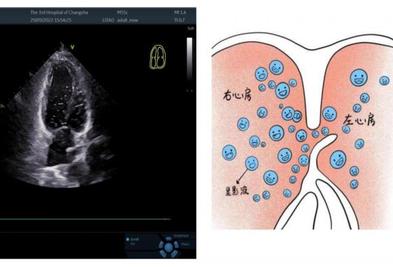

女人一帮孩子做作业就头疼,就诊检查竟发现心脏病。 长沙 41 近年来,年轻女性头痛反复发作,尤其是在辅导孩子作业时,这让她深受困扰。为了找出原因,缓解头痛,黎女性住在长沙市第三医院神经内科。 住院超声检查提醒黎女性无脂肪肝,颈部血管内中膜不厚,无斑块 2025-05-09